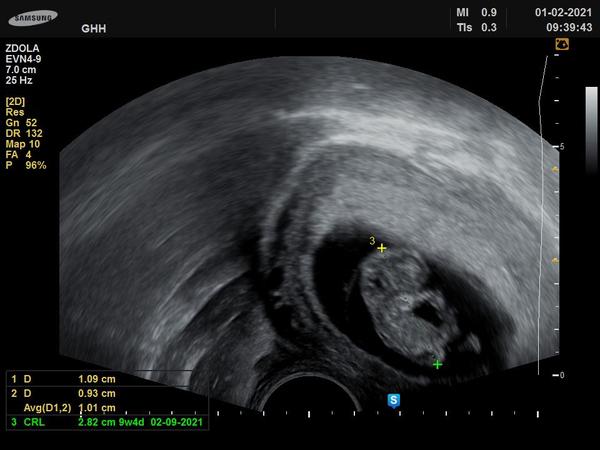

Ahoj holky, prosím, včera jsem začala 9tt. Od začátku těhu jsem měla citlivá, nafouklá prsa, ale včera prostě splaskly...stalo se to některé a těhu bylo v pořádku? Zůstávají mi slabé bolesti žaludku. Vím, že plaším, ale přesně v této době se u minulého těhu zjistilo zamlklé. Děkuji za anonym, ale chodí zde sestra a já zatím těhu nezveřejnila, na kontrolu jdu 1.2.